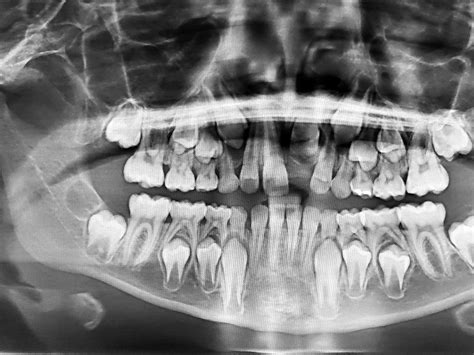

Radiografía dental en niños para diagnóstico y tratamiento.

Las radiografías digitales utilizan un sensor electrónico en lugar de la película tradicional, almacenando la imagen digital en un ordenador. Esta tecnología reduce la radiación entre un 80 y un 90% en comparación con las radiografías dentales tradicionales.